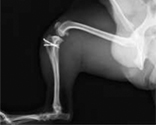

パピヨン×マルチーズ(10ヶ月齢、雌)グレードV 外科手術

- 【初診時症状】

- お散歩時跛行し、以降頻繁に外れるようになった

- 【手術】

- 脛骨粗面転位術、関節包縫縮を実施

- 【経過】

- 同居犬がおり、安静の維持が難しいため、術後2週間入院。術後4週間で屋内での運動制限を徐々に解除、8週間でお散歩の距離を少しずつ伸ばしていくも歩行問題なし。術後しばらくは右後肢の術創を気にして舐めていたが経過観察期間に徐々に消失。現在は制限なく生活。